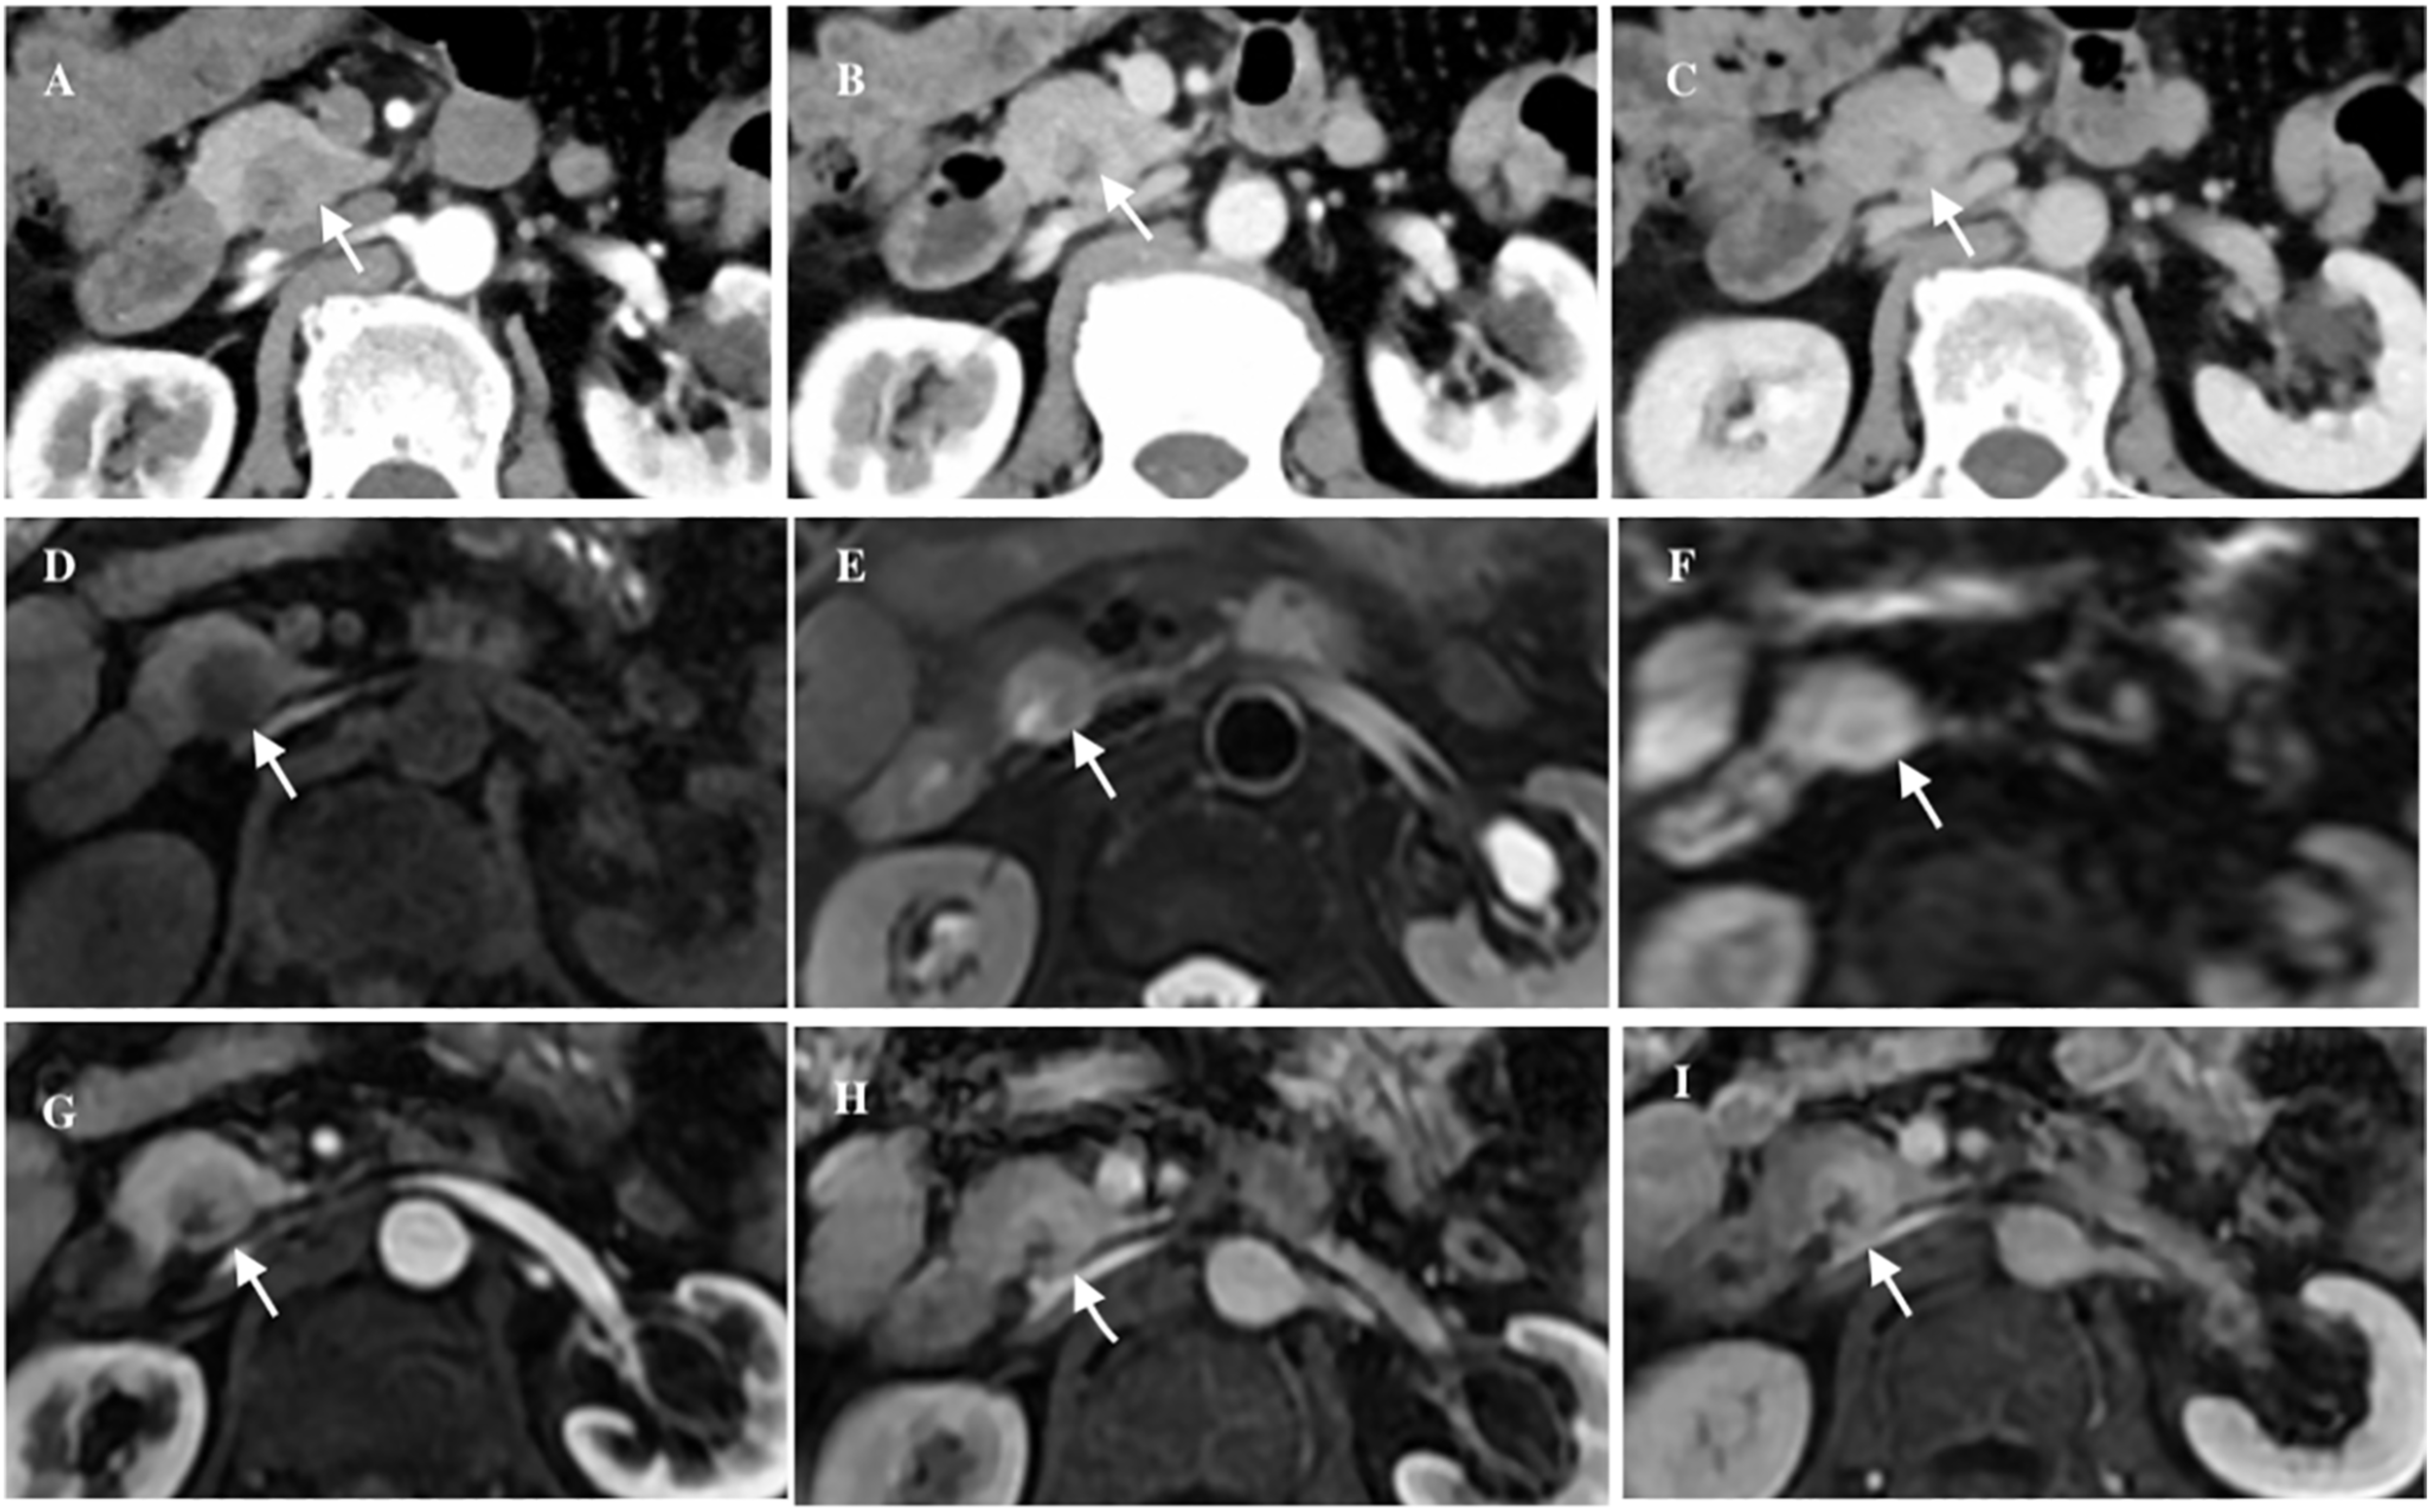

A 63-year-old male patient presented to our hospital with a chief complaint of ‘abdominal distension with abdominal pain for half a month’. He had no history of pancreatitis or systemic diseases, and additionally, he underwent right inguinal hernia repair surgery over 10 years ago. Laboratory investigations revealed unremarkable results, including normal levels of carbohydrate antigen 19-9 (CA19-9), carbohydrate antigen 12-5 (CA12-5), carcinoembryonic antigen (CEA), immunoglobulin G4 (IgG4), and amylase. Ultrasonography revealed a hypoechoic mass in the head of the pancreas with a clear boundary. CT imaging further demonstrated an inhomogeneous low-density mass located in the uncinate process of the pancreas, measuring approximately 21 × 18mm2 in size, and also exhibiting a distinct boundary. Post-contrast CT scans showed slight enhancement of the lesion in the arterial phase, followed by more pronounced enhancement in both the venous and delayed phases. Additionally, patchy areas of non-enhancement were observed within the lesion (Figure 1). No evidence of fat was detected within the lesions on imaging. Magnetic resonance imaging (MRI) further confirmed the presence of a space-occupying lesion in the uncinate process of the pancreas, which appeared to be disconnected from the main pancreatic duct. On T1-weighted images (T1WI), the lesion exhibited low-intensity characteristics, while on T2-weighted images (T2WI) and diffusion-weighted images (DWI), it demonstrated iso- to high-intensity signals. Contrast-enhanced MRI revealed a distinct delayed enhancement pattern of the lesion compared to the surrounding pancreatic parenchyma. Given these findings, we included neuroendocrine tumors (NETs) in our differential diagnosis. However, NETs did not correlate with all radiological findings. It is impossible to definitively rule out malignancy. Given the increased likelihood of malignancy or premalignancy in pancreatic incidentalomas, surgical intervention is the recommended treatment.

Figure 1

The axial abdominal CT enhanced scan revealed an inhomogeneous low-density lesion located in the uncinate process of the pancreas (white arrow), exhibiting a distinct boundary, slight enhancement in the arterial phase (A), obvious enhancement in the venous phase (B) and iso- to hyper-density in the delayed phase (C). Axial abdominal MRI plain scan showed a cystic and solid mass (white arrow), low intensity in T1WI (D), iso- to high-intensity in T2WI and DWI (E, F), and patchy cystic area could be seen inside. Axial abdominal MR enhanced scan showed the lesion (white arrow) had obvious progressive enhancement (G-I).